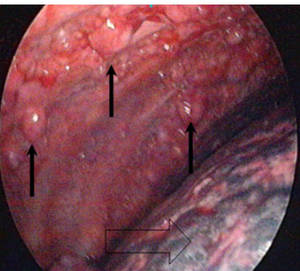

Häufige Symptome sind Luftnot und Schmerzen im Brustkorb. Untersuchungs-möglichkeiten bestehen in der Lungenfunktionsmessung und Röntgenaufnahmen (siehe Abb. 1). Weiterhin können eine Computertomographie (CT) Sonographie (Ultraschalluntersuchung), Magnetresonanztomographie, Pleurapunktionen, Spiegelung des Brustkorbes (Thorakoskopie, siehe Abb. 2) sowie die Entnahme von Gewebeproben  erforderlich sein.

Abb2: Thorakoskopie (Spiegelung des Brustkorbes)